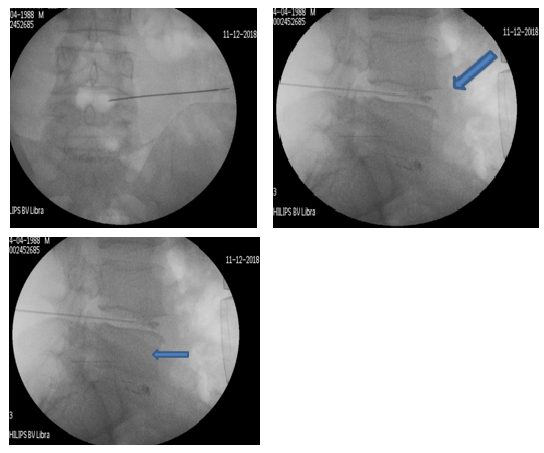

Χρησιμοποιώντας την εφαρμογή ραδιοσυχνοτήτων, εισάγεται, αρχικά, ένας οδηγός κάτω από ακτινοσκοπικό έλεγχο στον μεσοσπονδύλιο δίσκο και κατευθύνεται έμπροσθεν της κήλης. Μέσα από τον οδηγό εισάγεται ένα ηλεκτρόδιο, που η άκρη του έχει τη δυνατότητα κίνησης και στροφής 360ᵒ (Σχ. 1).

Το ηλεκτρόδιο υπερθερμαίνεται μέσα από μια πηγή σε θερμοκρασία 40ᵒC – 70ᵒC (coblation – low temperature ablation). Είναι μια μέθοδος, που χρησιμοποιεί ηλεκτρόδιο ραδιοσυχνοτήτων σε χαμηλές θερμοκρασίες για σύντομο χρονικό διάστημα 2’- 3’, χωρίς να καταστρέφει τους παρακείμενους ιστούς, αλλά δρα μόνον στο επιθυμητό σημείο του μεσοσπονδύλιου δίσκου (Σχ 2).

Περίπτωση 1: Ακτινοσκόπηση σε Διαδερμική Δισκοπλαστική με χρήση ηλεκτροδίου (RF) σε κήλη μεσοσπονδυλίου δίσκου Ο4-Ο5.